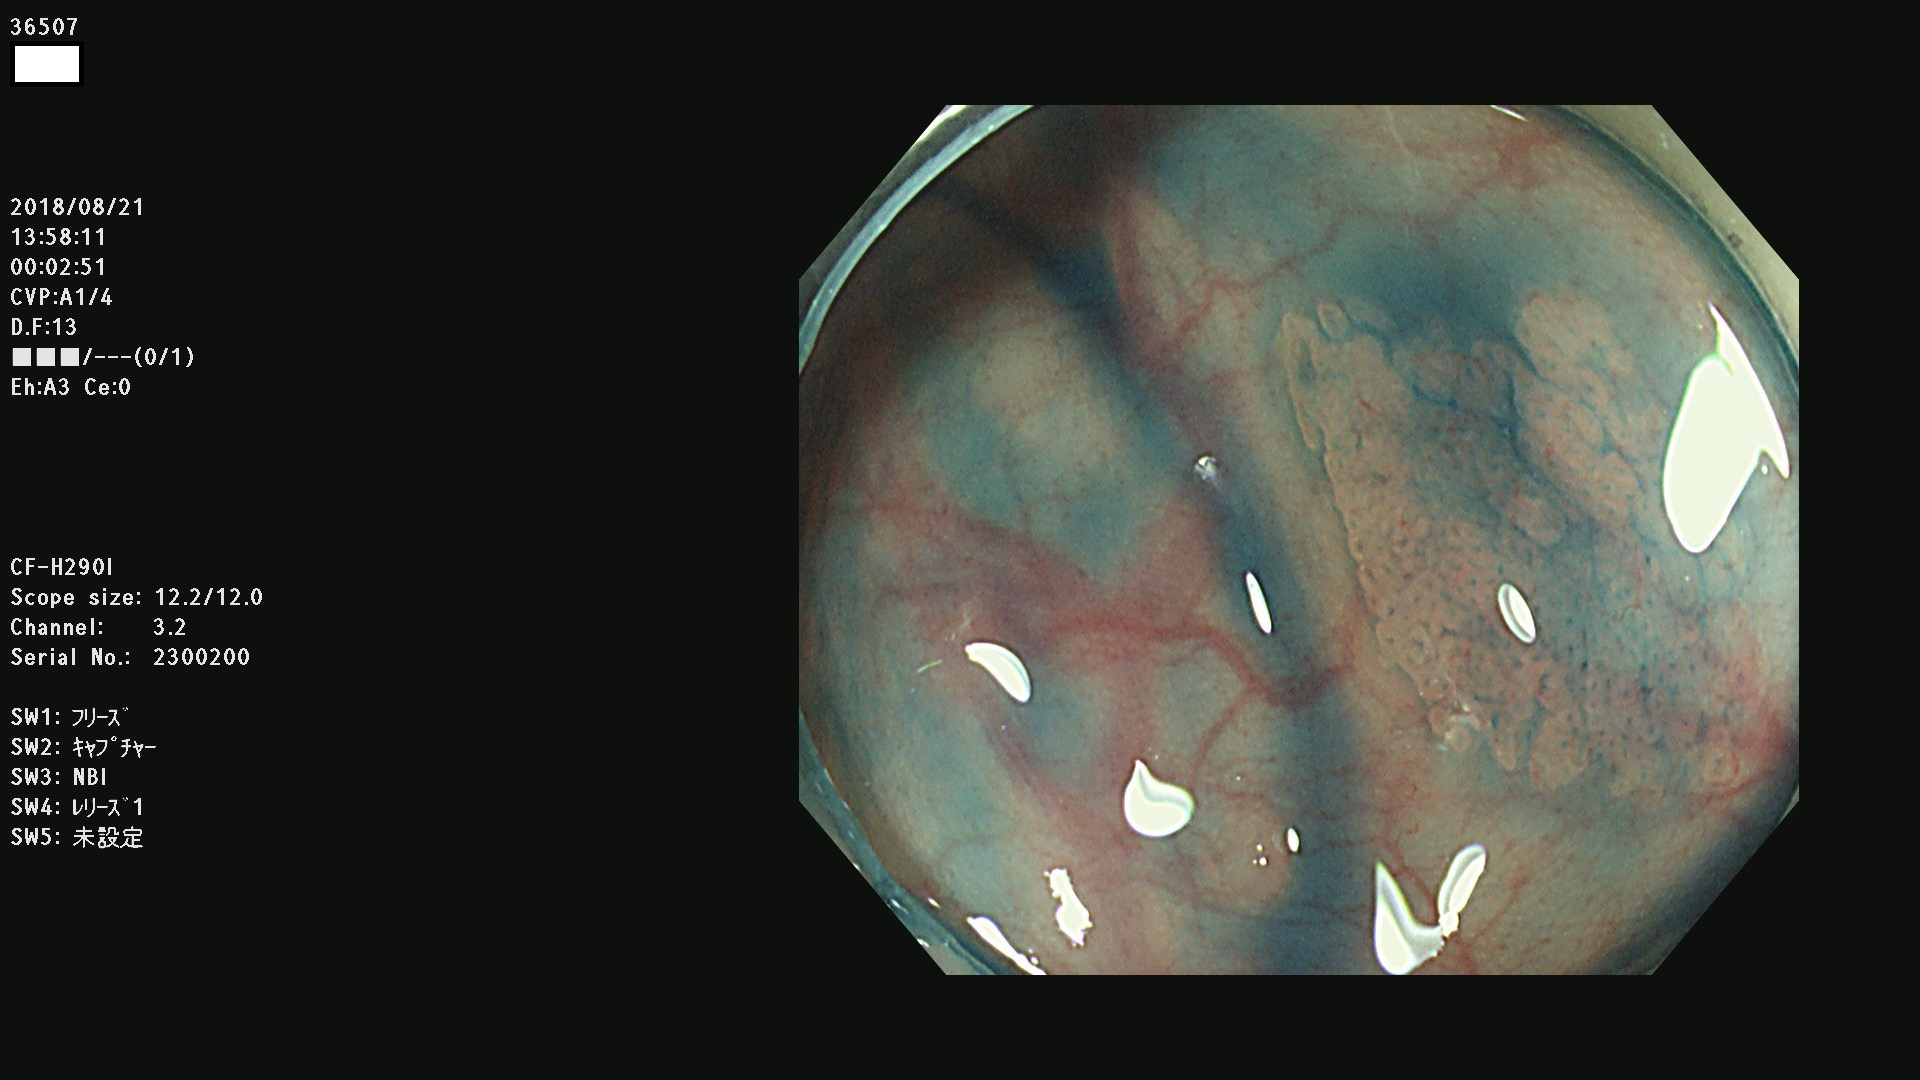

36500 36503 36504 36505 36507(SSAPのみ) 36508 36509 36510 36511 36514 36515 36517 36518 36520 36522(SSAPのみ) 36523 36524 36526 36528 36530 36531 36532 36533 36534 36535 36536 36538 36541 36542 36543 36544 36545 36546 36548 36550 36551 36554 36555 36556 36558 36559 36560 36561 36564 36565 36567 36568 36570 36572 36573 36574 36575 36576 36577 36578 36579 36580 36582 36584 36586 36591 36592 36593 36594 36595 36596 36597 36598

発見困難で危険性の高い平坦型病変(上記100名より抽出)

虫垂SSAP